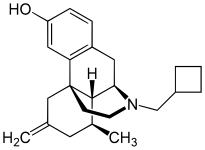

Morphinan derivatives

- Butorphanol—agonist/antagonist

- Nalbuphine—agonist/antagonist